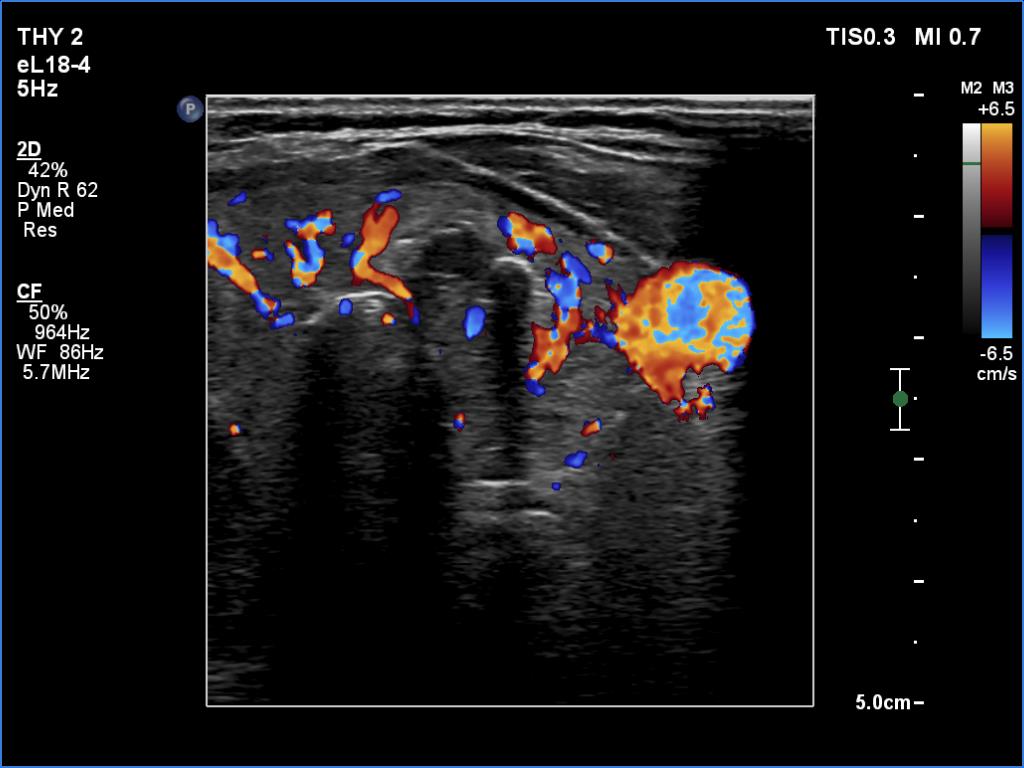

Ultrasonography. There was an irregular, large hypoechoic mass in the right lobe. The nodule has irregular, lobulated margins and was hard on elastography. A much smaller, similar nodule was in the lower-medial part of the left lobe.